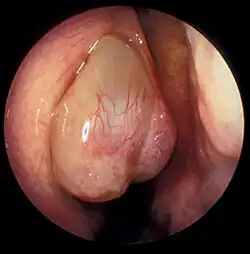

| A nasal polyp | |

Nasal polyps can be seen on physical examination inside of the nose and are often detected during the evaluation of symptoms. On examination, a polyp will appear as a visible mass in the nostril.[5] Some polyps may be seen with anterior rhinoscopy (looking in the nose with a nasal speculum and a light), but frequently, they are farther back in the nose and must be seen by nasal endoscopy.[12] Nasal endoscopy involves passing a small, rigid camera with a light source into the nose. An image is projected onto a screen in the office so the doctor can examine the nasal passages and sinuses in greater detail. The procedure is not generally painful, but the person can be given a spray decongestant and local anesthetic to minimize discomfort.[13]